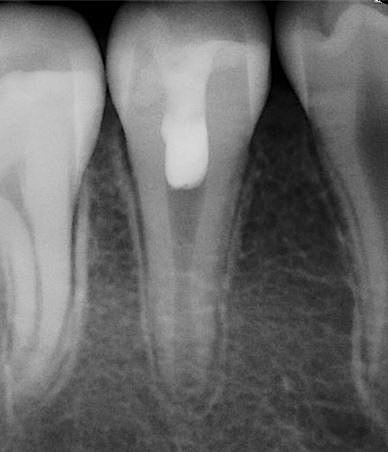

Following the induction of bleeding, a resorbable collagen matrix is placed over the blood clot. Next, a bioceramic material is placed directly over the collagen matrix, a glass ionomer is placed over the bioceramic material, and a final composite or amalgam restoration is placed over the glass ionomer. Once the restoration is complete, a final radiograph is taken (Figure 3 and Figure 4), and the patient is put on 6-month recall for up to 3 years, as dictated by the healing process (Figure 5).25

(4.) Immediate postoperative radiograph after second visit for regenerative endodontic treatment on tooth No. 29.

Figure 4